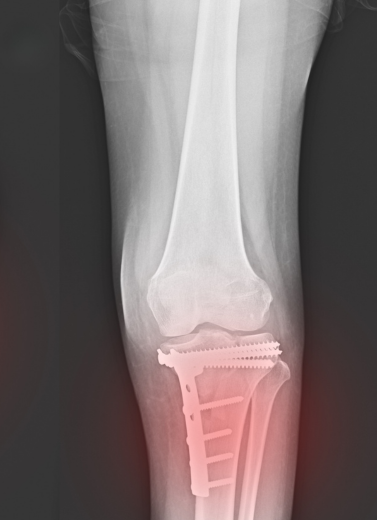

Plating & Nailing Techniques

Bone Grafting & Reconstruction

Non-union & Malunion Fracture Correction

All surgeries are performed with infection-controlled OTs, digital X-ray support, and post-op rehab planning.

We treat each trauma case with urgency and care, beginning with imaging (X-ray/CT), followed by a personalized treatment plan. Whether surgical or conservative, our aim is quick stabilization, early mobilization, and pain control.